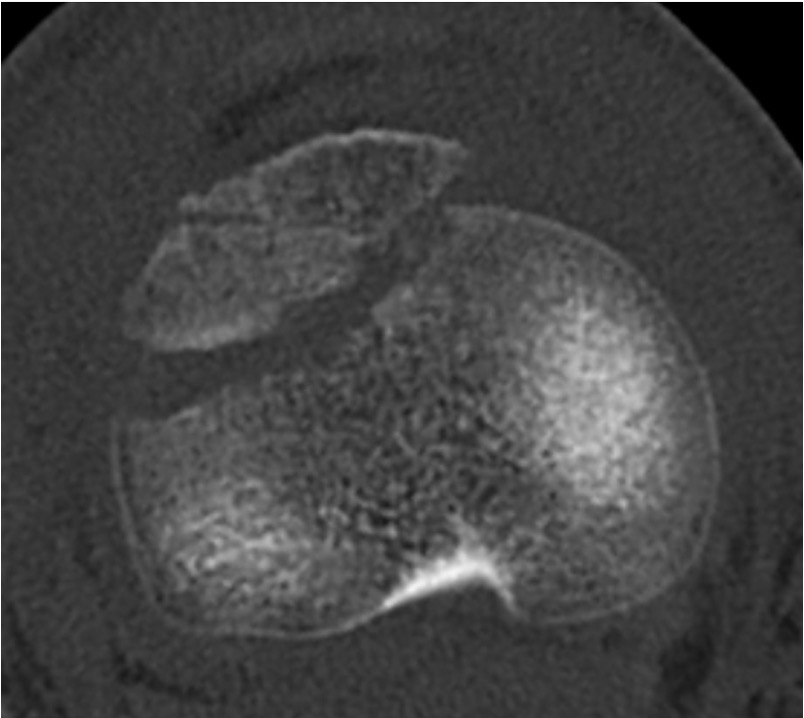

CT / MRI scan

CT scan - ensure fracture doesn't involve the physis / disrupt articular surface

Comminuted Type III